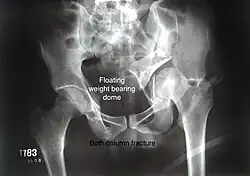

Combined both column fractures These are the most complex injuries. Here the weight bearing roof or dome of the acetabulum is a floating piece. This adds to complexity of management.

Diagnosis

All three x-ray views plus CT scan is a must for diagnosis and management of this complex injury.